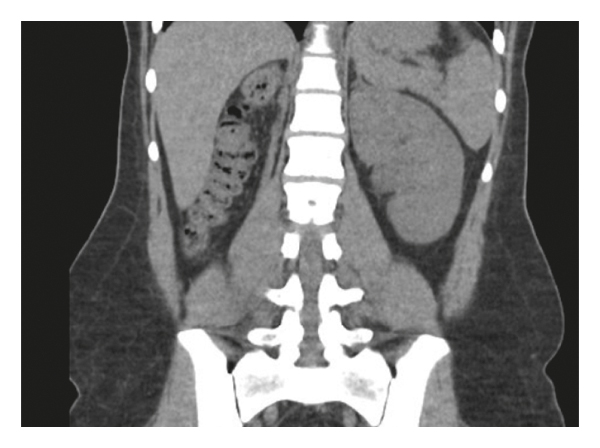

A previously healthy 22-year-old female was diagnosed with gestational diabetes after failing her 1-hour glucose tolerance test at 28 weeks gestation with a blood glucose level of 241. Elevated glucose levels were noted on random basic metabolic panels done prior to pregnancy, but the patient did not meet criteria to diagnose diabetes mellitus. Patient had no other symptoms at the time of the abnormal oral glucose tolerance test. The pertinent medical history prior to pregnancy included ultrasounds showing a small multicystic dysplastic right kidney. Patient’s left kidney showed compensatory hypertrophy and a small midpole cyst (Figure 1). Kidney function is followed by nephrology and has been unremarkable. The family history is positive for polycystic kidney disease in her mother and maternal grandmother.

Patient did experience other extrapancreatic symptoms that included low magnesium (1.3 mg/dl), high uric acid (11.1 mg/dl), and pancreatic hypoplasia noted on previous CT done two years prior to her diagnosis. CT scan was done to rule out renal stones and did show pancreatic tail hypoplasia (Figure 2). Patient’s most recent blood work done 6 weeks following delivery is given in Table 1. She delivered a healthy baby girl via spontaneous vaginal delivery at 39 weeks of gestation weighing 3170 g with APGAR score of 8 and 9 at 1 and 5 minutes, respectively. Her daughter has normal kidneys.